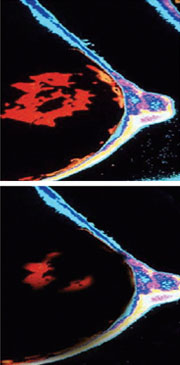

Following light administration tumor cells are damaged or destroyed. Tumor cells (orange).

NIR imaging of breast cancer following Next Generation PDT therapy.